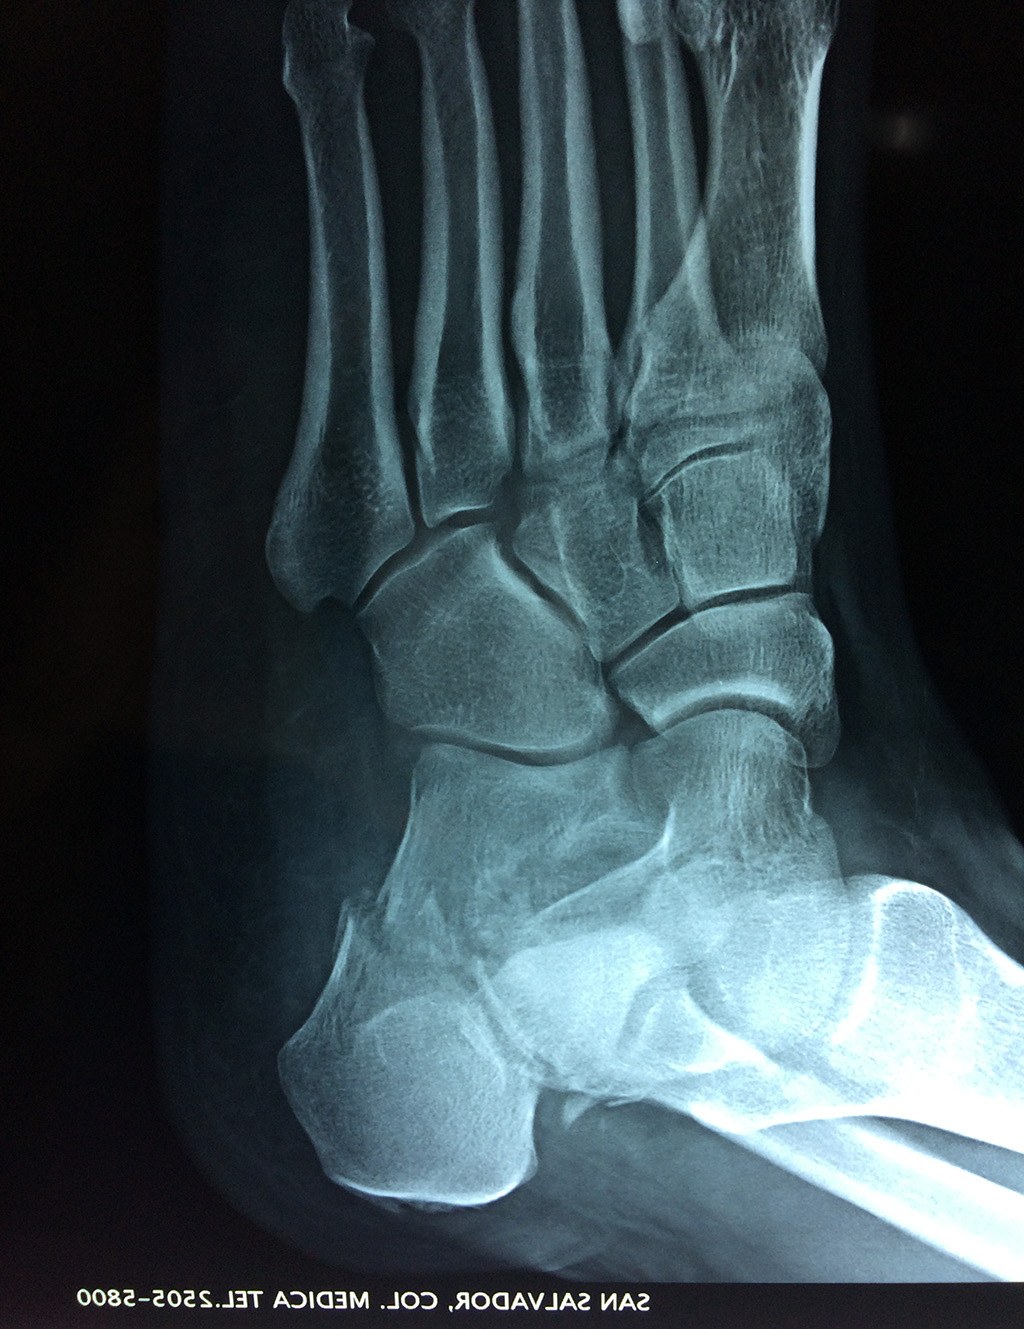

El calcáneo (del latín Os calcis) es un hueso del pie (tarso), corto, asimétrico, de forma cúbica irregular, con seis caras: superior e inferior, laterales y anterior y posterior, de las cuales dos son más o menos articulares.

Este hueso constituye el talón del pie. Se encuentra en la parte inferior de la primera fila del tarso. Se articula con el astrágalo por arriba y con el cuboides por delante. Constituye el primer punto de apoyo del pie durante la marcha, situándose en una de las zonas peor irrigadas del cuerpo y protegido plantarmente por la almohadilla plantar de tejido adiposo, con función amortiguadora.

En su cara posterior recibe la inserción del tendón más plantar, implicada en diversas enfermedades como la fascitis o el espolón calcáneo. La posición del calcáneo en relación al astrágalo (articulación subastragalina) y al suelo determinan la posición de retropié en varo, en valgo o neutra.